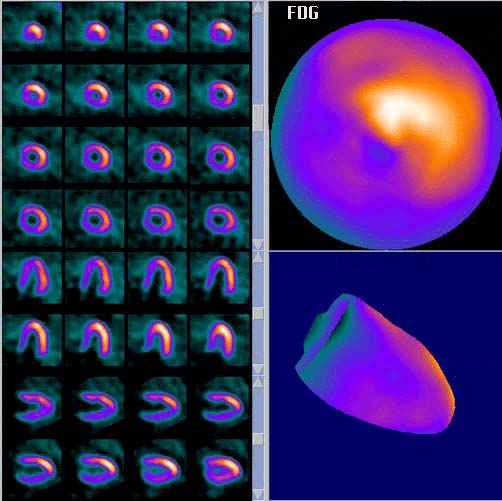

- Age/Sex: 76F

- Images: (click each image to

magnify)

- X-CT

-

- Nuclear

|

Tl-201 Early

|

Tl-201 Delayed

|

F-18 FDG

|

丂

偁側偨偺恌抐偼 What

is your first impression?